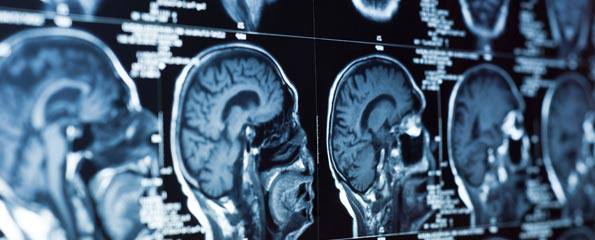

Boğaziçi Üniversitesi Biyomedikal Enstitüsü’nde doktora çalışmalarını sürdüren Abdullah Baş, ekipçe biyomedikal alanında çalıştıklarını belirterek, “Hepimiz biyomedikal mühendisiyiz. Beş kişinin üçü halihazırda yapay zekâyla ilgileniyor. Bu yarışmanın başvuruları açıklandığında, rapor istenen aşamayı geçtikten sonra yarışma özelinde çalışmaya başladık. Üniversitede de benzer olarak medikal görüntüleme üzerine çalışıyoruz. Ben beyin MR’ı konusunda araştırmalarımı sürdürüyorum” diyor.

“Sağlıkta Yapay Zekâ Yarışması için bilgisayar tomografi (BT) görüntülerinde beyin dokusunda inme, kanama ve iskemiyi segmente edecek bir yazılım oluşturmamız bekleniyordu. İlk önce sadece inme olup olmadığının sınıflandırmasının beklendiği bir ön eleme aşaması vardı. O aşamayı geçenlerle de segmentasyon aşamasına geçiliyordu. İnme, iskemi ve kanamayı sınıflandıracak bir model bekleniyordu. Biz açıkçası finale kalmayı bekliyorduk, o açıdan biraz hayal kırıklığımız oldu. Biz daha optimizasyonları yapmamışken yüzde 90’lık bir başarı sağlamıştık sınıflandırmada. Birinci olanlar yüzde 96 başarı sağlamış. Optimizasyonları yaptıktan sonra çok rahatlıkla benzer bir başarı yakalayabilirdik.”